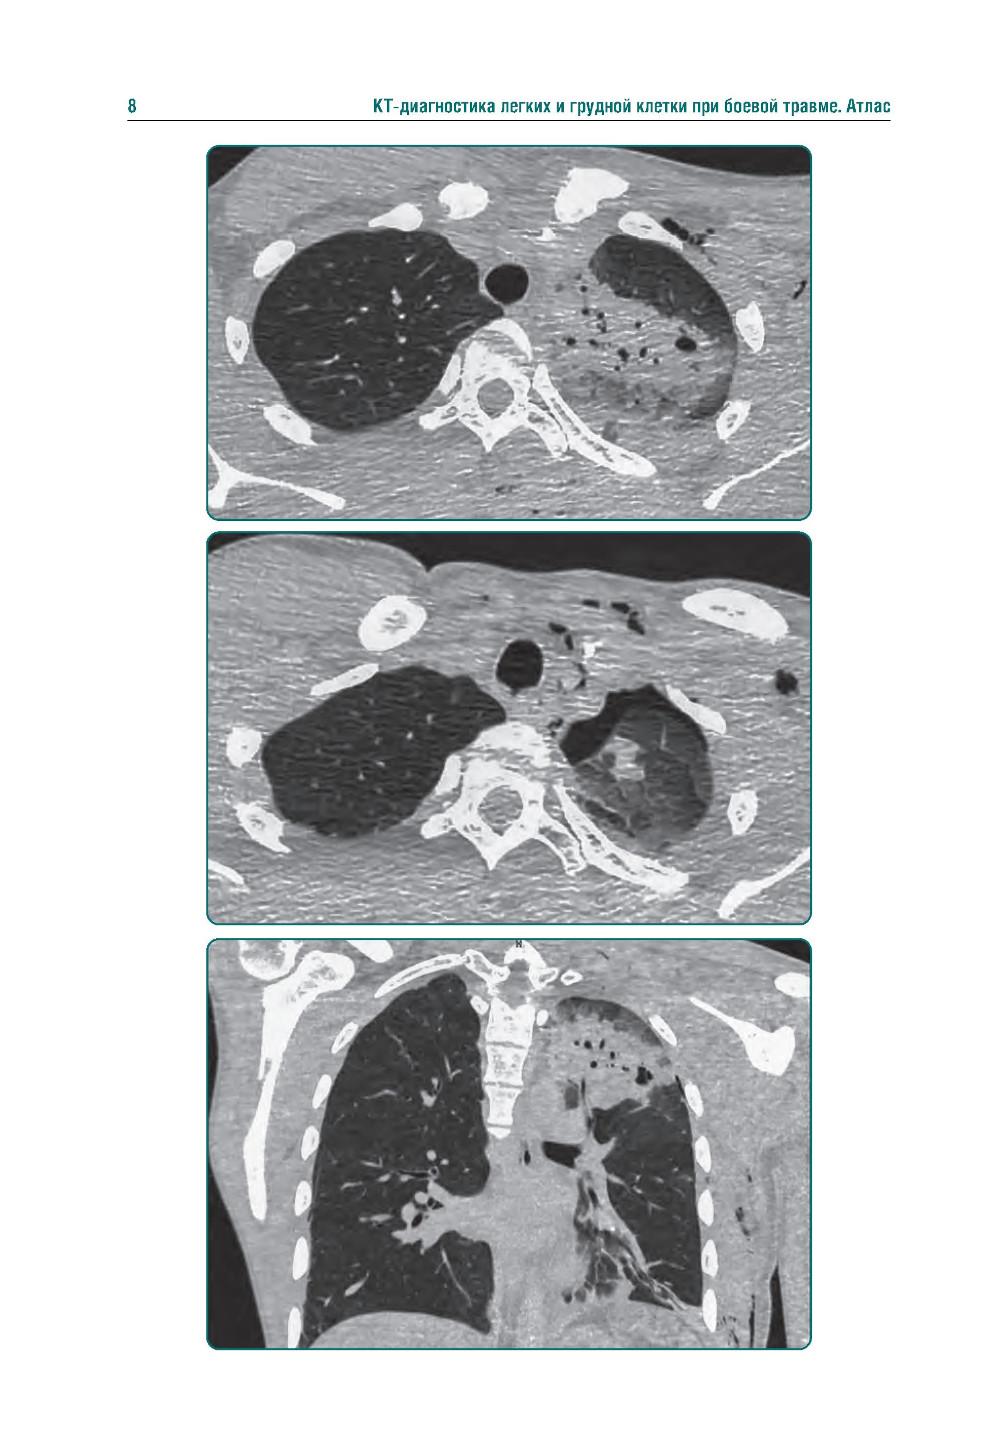

Аннотация: КТ-признаки поражения легких и грудной клетки при боевой травме: атлас

Издание представляет собой первый в Российской Федерации атлас, иллюстрирующий различные виды поражения легких, плевры и других структур грудной клетки у пациентов с боевыми ранениями. В современных условиях количество таких пациентов увеличивается, поэтому существенно возрастает значимость различных видов боевых травм, в том числе повреждений грудной клетки. В атласе представлены уникальные КТ-изображения различных видов боевой травмы грудной клетки, полученных в условиях современных вооруженных конфликтов. Помимо описания характера, условий получения травмы и выявленных повреждений, есть возможность просмотра изображений в формате DICOM. Атлас предназначен для врачей-рентгенологов, торакальных хирургов, пульмонологов, а также врачей других специальностей, занимающихся диагностикой и лечением пациентов с боевыми травмами.| Издательство | ГЭОТАР-Медиа |